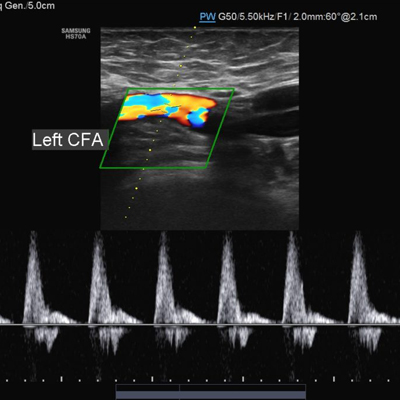

Venous Doppler

A venous Doppler ultrasound is a diagnostic test used to check the circulation in the large veins in the legs (or sometimes the arms). This exam shows any blockage in the veins by a blood clot or “thrombus” formation.